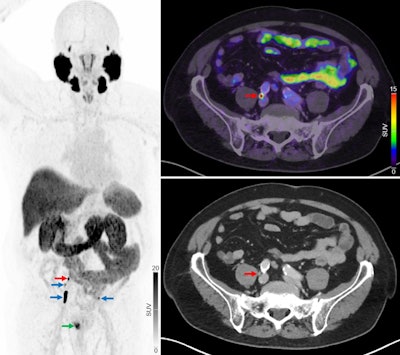

Primary staging of a patient with high-risk prostate cancer. Initial F-18 NaF-PET/CT showed no regional or distant metastases. The patient later underwent radical prostatectomy with extended pelvic lymph-node dissection. In a blinded project review, F-18 PSMA-PET/CT revealed multiple intrapelvic lymph node metastases (blue arrows) and 1 lymph node metastasis near bifurcation of right common iliac artery (red arrows). Primary prostate lesion is also visible (green arrow). Three months postoperatively, the patient’s PSA remained elevated (0.67 ng/mL), and bicalutamide therapy was started.Primary staging of a patient with high-risk prostate cancer. Initial F-18 NaF-PET/CT showed no regional or distant metastases. The patient later underwent radical prostatectomy with extended pelvic lymph-node dissection. In a blinded project review, F-18 PSMA-PET/CT revealed multiple intrapelvic lymph node metastases (blue arrows) and 1 lymph node metastasis near bifurcation of right common iliac artery (red arrows). Primary prostate lesion is also visible (green arrow). Three months postoperatively, the patient’s PSA remained elevated (0.67 ng/mL), and bicalutamide therapy was started.Journal of Nuclear MedicineOverall, treatment plans were subsequently modified for 21 (13%) of the 160 patients, with 19 shifted to therapies targeting more advanced stages of disease and two reclassified as candidates for curative treatment. Among the 69 patients initially considered for curative treatment, eight (12%) were reclassified to receive noncurative treatment.